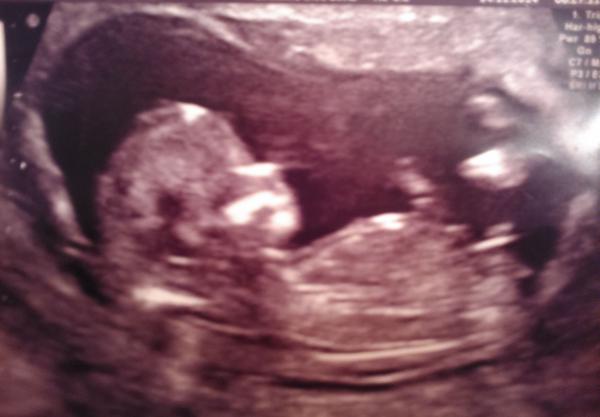

zapomela jsem napsat hned -- na další kontrole - 18 . tyden mi doktorka potvrdila chlapecka. dokonce mi místo ukazovala, fakt to tak uz vypada. za tyden jdu na velky utz, tak snad bude i další fotka. hlavne at je prdola zdravi 🙂). pokud se u nas kluk potvrdi, rekla bych, ze funguje i to rozeznavani s tim výběžkem --tedy miri nahoru u kluka, miri od telicka u holky. 🙂)

já už holčičku i kluka mám, tak nám je to jedno,hlavně aby bylo mimi zdravé 🙂 mě u holčičky na 17tt na 4D utz řekla dr. že na 70% holka a potvrdilo se to, na 16tt my řekli u syna že tohle je jasný kluk.No a teď, že to na holčinu vypadá spíš, než na kluka, že kluci jsou jasný ale u holek se to poznává hůř 🙂 tak uvidíme ve 20 tt 😉